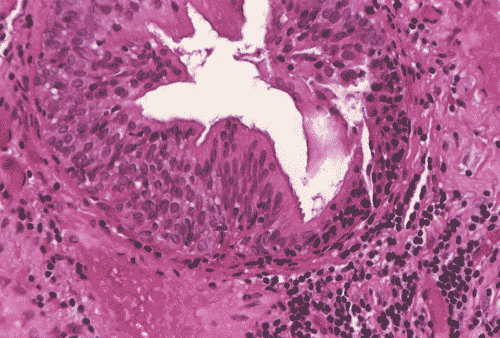

The biopsy material showed polypoid fragments with cystically dilated glands lined by columnar to cuboidal cells (Panel A, B, and C). Some of the glands were lined by transitional epithelium (Panel D), some were lined by a mixed transitional epithelium and mucin producing columnar epithelium (Panel E), and some were lined entirely by mucin producing columnar epitheliuim (Panel F) that closely resembled colonic epithelium. A mild to moderate degree of chronic inflammatory cell infiltration was also present. A mixed population of mucin producing columnar epithelium with transitional epithelium was also noted in many of the non-glandular surface epithelium (Panel G). No dysplasia was found.